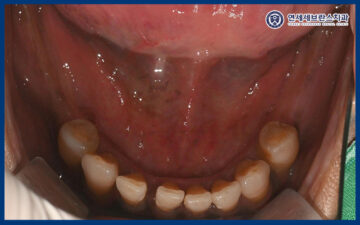

<잇몸 회복 양상 빠름>

약 2주 후 내원하셔서

회복 양상을 확인해 보았는데요.

네비게이션 가이드로 수술해서

발치 후 임플란트를 식립 했음에도 불구하고

2주 만에 잇몸이 거의 나은 양상을 볼 수 있었습니다.